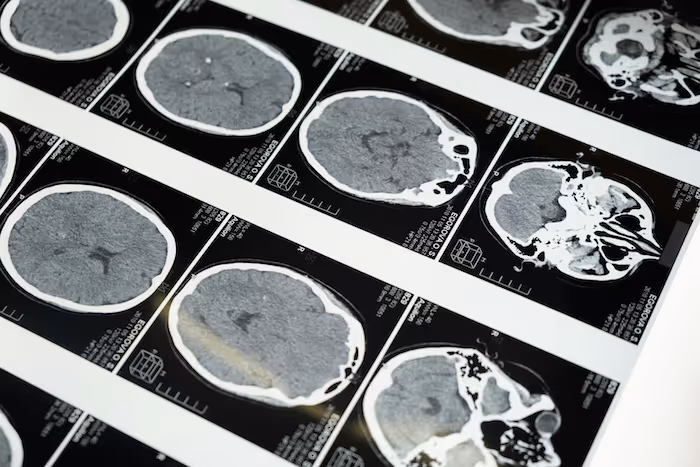

Servicios de anotación de resonancia magnética (MRI) para IA médica: segmentación, clasificación y detección de hallazgos con guías claras y control de calidad.

Los conjuntos de datos de IRM requieren anotaciones precisas y estructuradas para respaldar los sistemas de IA que analizan los tejidos blandos, las estructuras neurológicas, las regiones musculoesqueléticas y los patrones relacionados con la patología. La resonancia magnética presenta desafíos únicos, como el contraste variable, la complejidad anatómica y la variación entre secuencias.

Adaptamos los flujos de trabajo a las secuencias T1, T2, FLAIR, DWI, DTI, IRM con contraste mejorado y otras. Nuestras tareas de anotación por resonancia magnética incluyen la segmentación de la región cerebral, el rastreo de los vasos sanguíneos, el marcado de las lesiones, el etiquetado de la estructura musculoesquelética, la segmentación de los órganos, la anotación de la región tumoral, el etiquetado de la columna vertebral y la clasificación de los tejidos. Admitimos tanto la anotación basada en cortes en 2D como los flujos de trabajo volumétricos en 3D que mantienen la alineación en todo el volumen de la resonancia magnética. El control de calidad incorpora la revisión en varios pasos, las comprobaciones de coherencia en todas las secuencias y los ciclos de corrección específicos.

Anotamos la materia blanca, la materia gris, los ventrículos, los vasos, las lesiones y las estructuras específicas de la región para la investigación y los modelos de neuroimagen asistidos por IA.

Anotación de tumores y lesiones

Anotamos las regiones tumorales, los hallazgos sospechosos y las zonas de lesión segmentadas de acuerdo con las reglas específicas del proyecto y los ciclos de revisión.